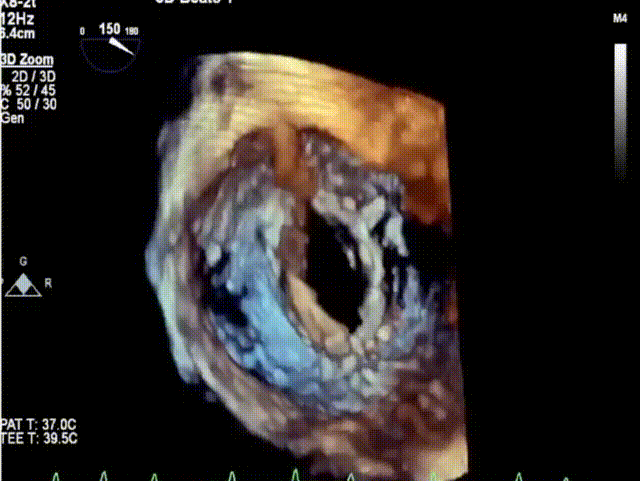

术后即刻超声评估

2021年12月22日,四川大学华西医院心脏内科陈茂、冯沅教授联合心脏外科蒙炜教授、麻醉科朱涛、陈果教授等组成的多学科团队完成了HighLife TSMVR技术的亚洲首例临床应用。手术过程顺利,人工瓣膜植入位置理想,术后即刻二尖瓣返流完全消失,无左室流出道梗阻,患者恢复良好。该例手术亦是亚洲地区开展的首例经房间隔二尖瓣置换术!

该例患者为74岁女性,因劳力性呼吸困难就诊,近期反复发作急性左心衰竭住院治疗,并伴有持续性房颤、高血压、糖尿病等疾病。超声心动图评估提示二尖瓣中重度返流、轻中度主动脉瓣返流与轻度三尖瓣返流,LVEDD 52mm,LVESD 40mm,LVEF 47%。二尖瓣返流机制为Carpentier I+IIIa型,有效返流口面积为0.31cm2,返流量47mL,瓣口面积为3.7cm2。因考虑外科手术风险高危,同时由于二尖瓣瓣口面积较小不适宜经导管二尖瓣缘对缘修复术,多学科团队讨论后决定使用Peijia HighLife TSMVR系统行经房间隔二尖瓣置换术。